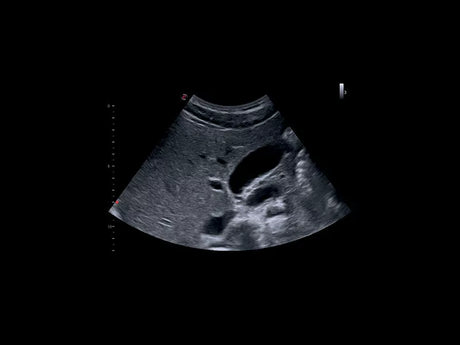

Les échographes Esaote offrent une restitution d’image d’une grande précision, permettant un diagnostic fiable dans toutes les spécialités. Le traitement numérique optimise le contraste et la netteté, réduisant les artefacts et améliorant la détection des tissus pathologiques. Ces performances sont particulièrement appréciées en gynécologie, où la lisibilité des structures pelviennes ou obstétricales est déterminante.

Un gynécologue privilégiera un échographe offrant une résolution d’image très fine et une compatibilité avec des sondes endocavitaires. Un kinésithérapeute ou un médecin du sport recherchera plutôt un appareil portable, léger et rapide à mettre en route. Les praticiens généralistes apprécieront la polyvalence et la facilité d’entretien, tandis que les vétérinaires auront besoin d’un système robuste et facilement transportable.